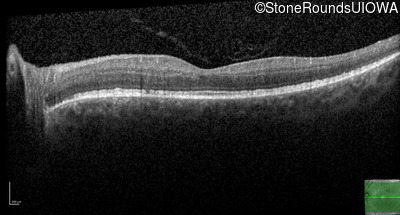

Optical Coherence Tomography - Right - 20/25 -1

Exemplar / OCT Stack